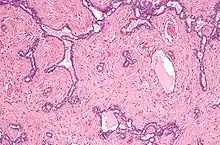

Micrograph of the rete testis. H&E stain.

The rete testis is the network of interconnecting tubules where the straight seminiferous tubules (the terminal part of the seminiferous tubules) empty. It is located within a highly vascular connective tissue in the mediastinum testis.[2] The epithelial cells form a single layer that lines the inner surface of the tubules. These cells are cuboidal, with microvilli and a single cilium on their surface.[3]